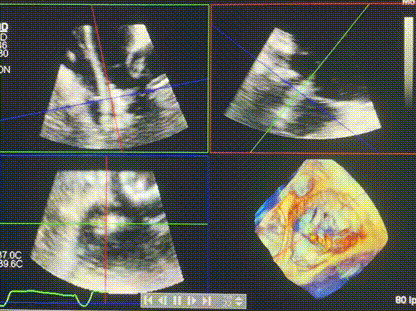

術(shù)前超聲提示重度三尖瓣反流

接受本次LuX-Valve Plus治療的是一位三尖瓣重度反流的高齡女性,患者早前曾由于二尖瓣疾病行經(jīng)導(dǎo)管二尖瓣置換術(shù),植入Tendyne瓣膜一枚,且有ICD植入史。術(shù)前CT分析結(jié)果顯示,瓣環(huán)大小為47.6mm,血管無明顯迂曲和鈣化。由于患者三尖瓣解剖結(jié)構(gòu)復(fù)雜,二尖瓣位人工瓣膜造成的超聲偽影和ICD導(dǎo)線的干擾使得歐洲沒有其他合適的商業(yè)化和臨床試驗的產(chǎn)品可以對其進行治療。經(jīng)過Rodrigo Estévez-Loureiro教授團隊的詳盡術(shù)前評估,認為LuX-Valve Plus經(jīng)導(dǎo)管三尖瓣置換系統(tǒng)可以對該患者進行有效的治療。因此,Rodrigo Estévez-Loureiro教授團隊最終決定使用這一中國創(chuàng)新器械為患者進行手術(shù)。法國波爾多里爾大學(xué)附屬醫(yī)院的Thomas Modine教授與加拿大圣保羅醫(yī)院的Anson Cheung教授全程線下指導(dǎo)本次手術(shù)。